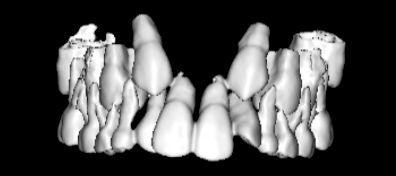

治療法:上顎急速拡大装置+クリアスナップ+フェイスマスク+上顎3番は開窓牽引CT写真にて位置確認

骨年齢は実年齢よりも低めなので、今後下顎の旺盛な成長が見込まれます。

検査時のレントゲン分析では、上下顎の関係は、上顎の劣成長があり下顎前突傾向という値がでておりましたが、前歯ジャンプ後はフェイスマスクの効果もあり、上下顎の関係は正常化しています。

上顎が若干優位になっていますので、今後の下顎の成長のための貯金になっているくらいです。